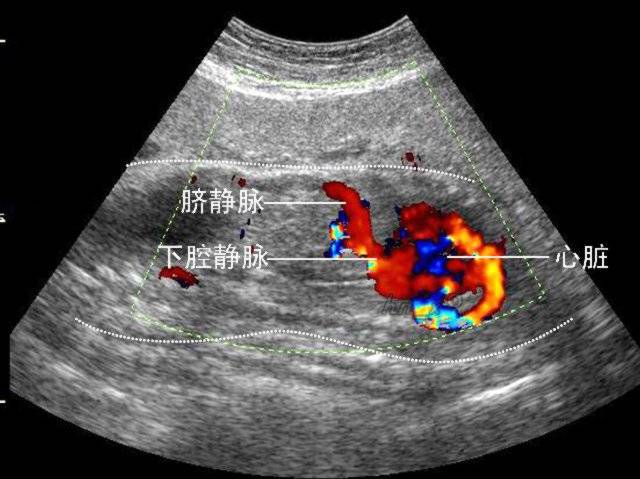

心脏彩超

应用超声波扫描技术观察心血管结构、血流动力学状况及心功能的一种无创伤性检查方法,它可了解心脏各组成部分的形态以及功能状态,了解心脏内畸形位置、大小、大血管的关系以及其他畸形情况和病变程度。血管情况、病灶内血流血供情况-良恶性病变鉴别。

出现胸闷、胸痛、心悸等症状时,心电图是最简单易行的检查,但是心电图无法了解心脏内部的结构及功能。而心脏彩超可以观察心脏的运动情况,包括心肌的收缩、舒张,瓣膜的开放、关闭,血液流动的速度、方向,心脏与大血管的连接关系以及心脏及心包内的异常声像。因此,凡是有胸闷、胸痛、心悸症状的人群,建议做心脏彩超的检查。